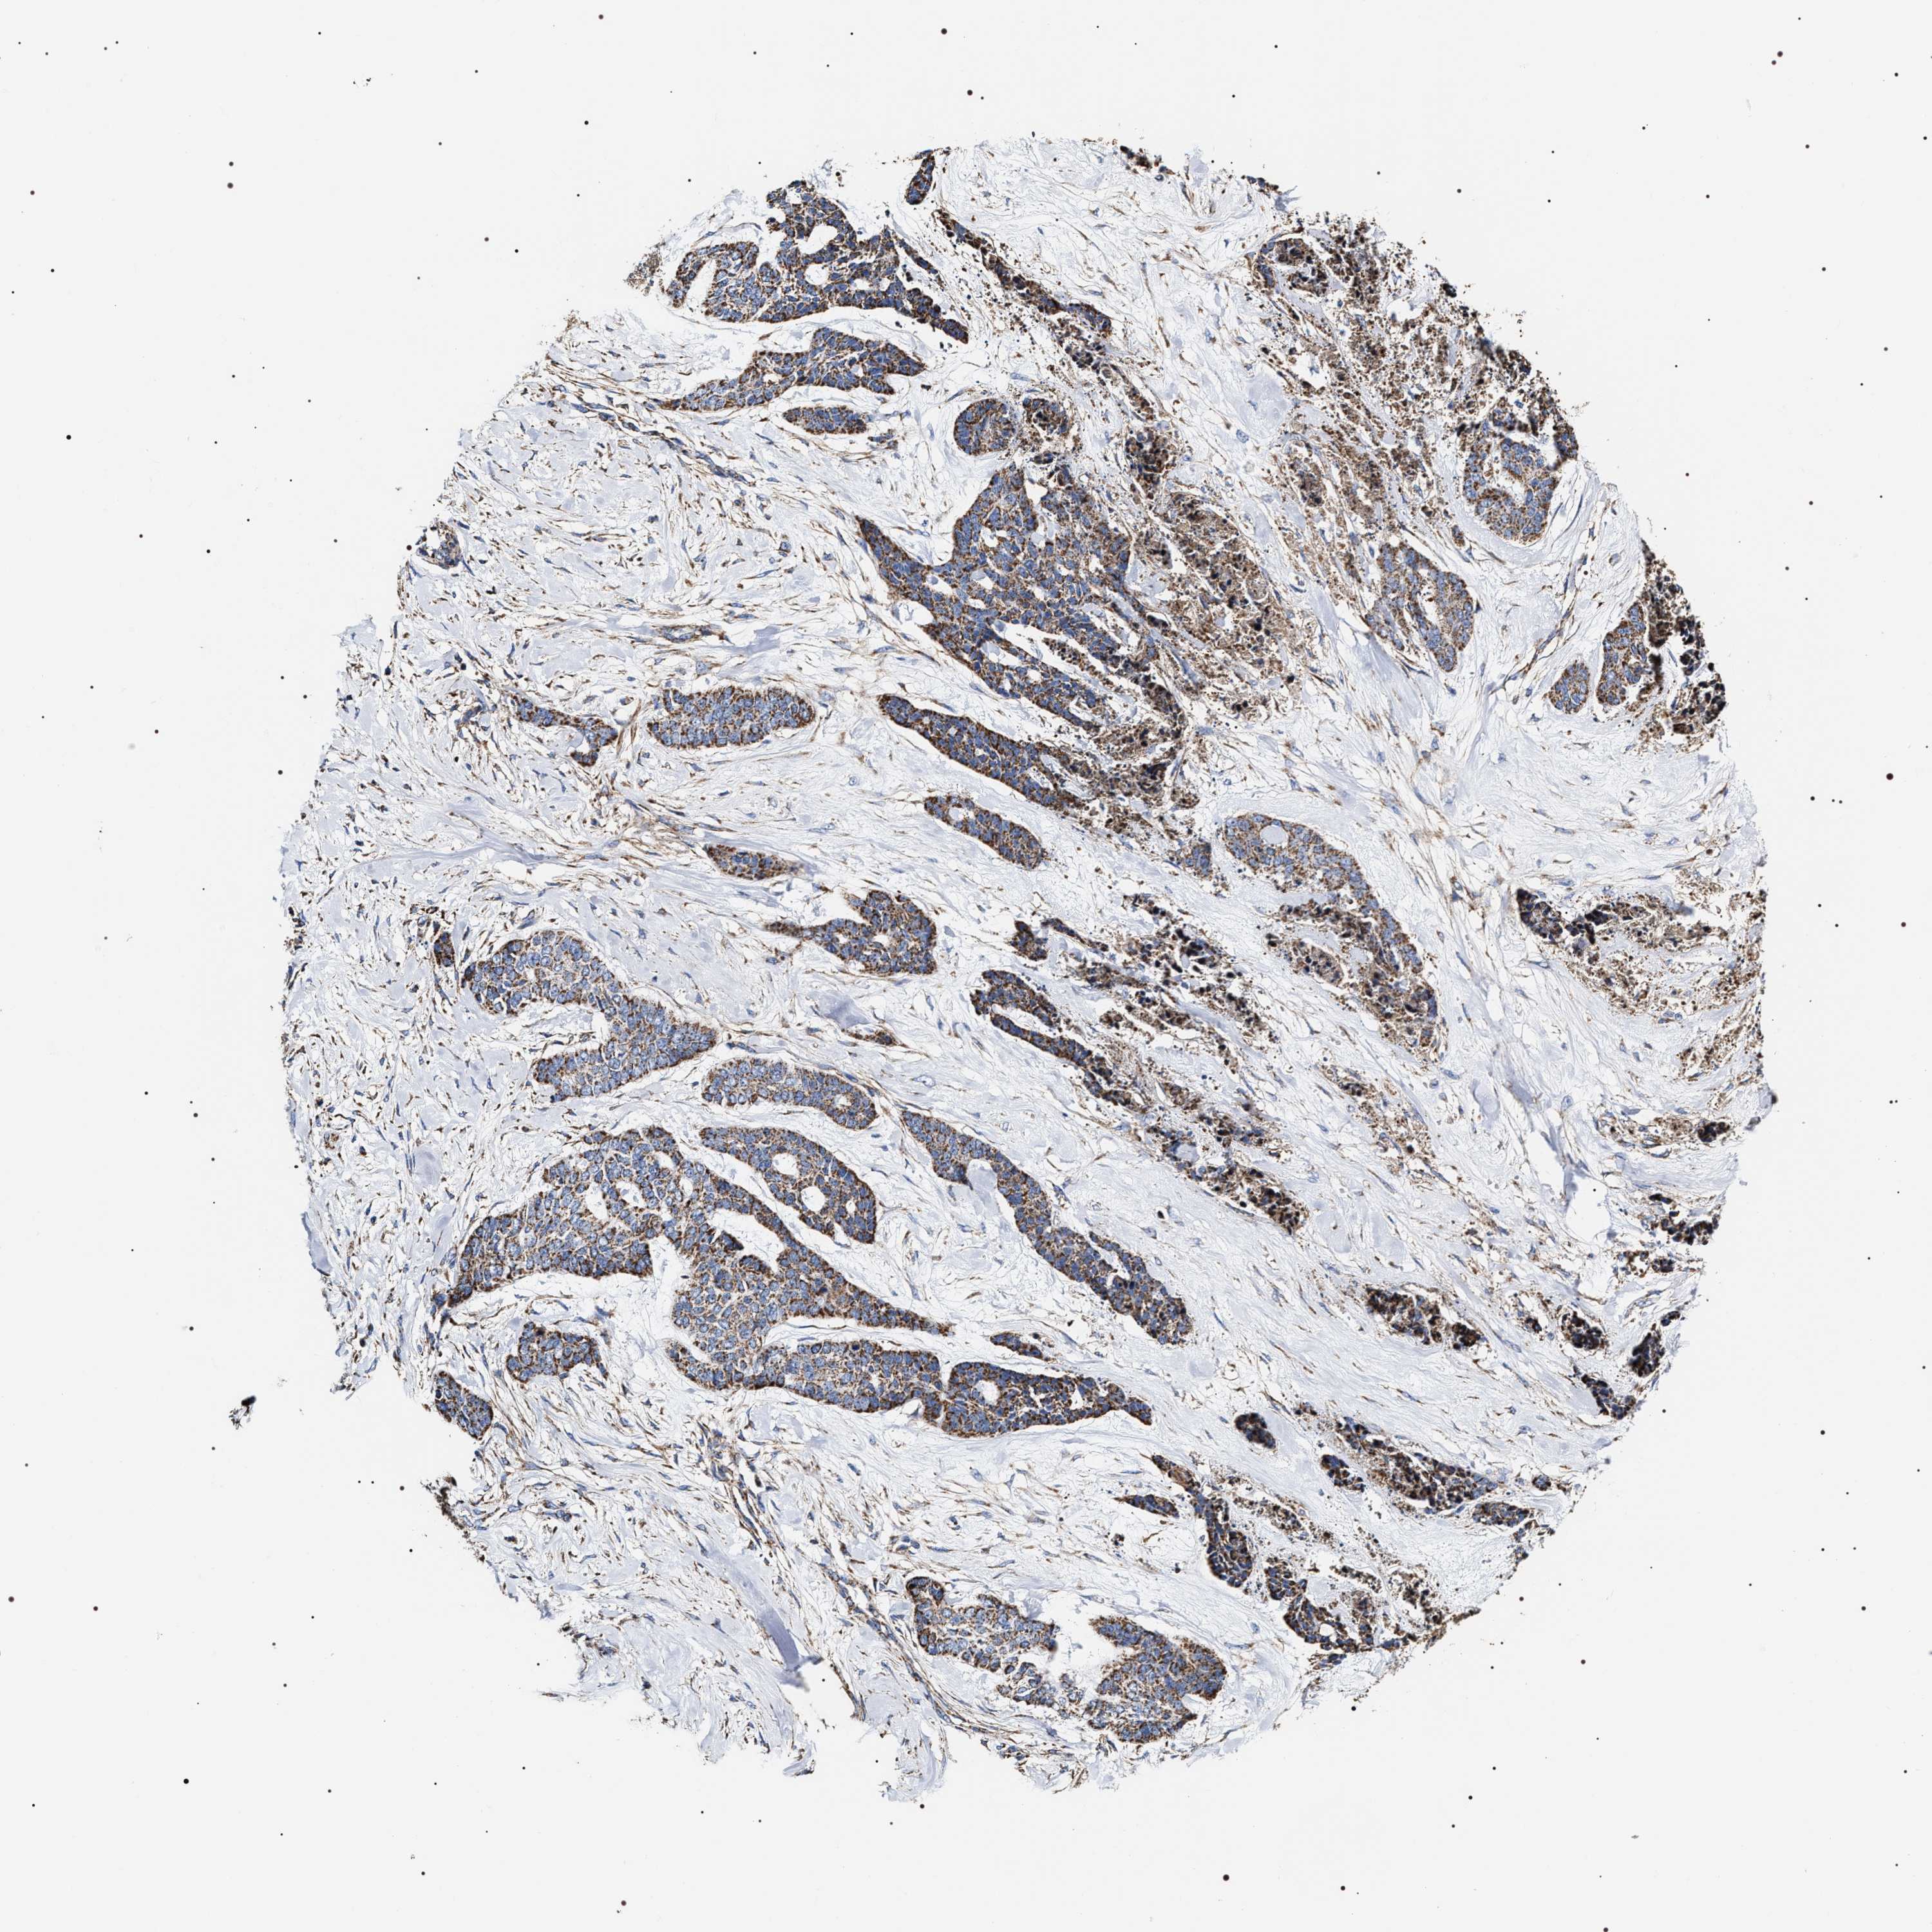

Basal cell and squamous cell cancer

SKIN CANCER - Protein expressioni

A mouse-over function shows sample information and annotation data. Click on an image to view it in a full screen mode. Samples can be filtered based on level of antibody staining by selecting one or several of the following categories: high, medium, low and not detected. The assay and annotation is described here.

Each image is clickable and will lead to virtual microscopy that enables deeper exploration of all samples and also displays staining intensity scores, fraction scores and subcellular localization as well as patient and tissue information for each sample.

Antibody HPA020300

Staining

High

Medium

Low

Not detected

Intensity

Strong

Moderate

Weak

Negative

Quantity

>75%

75%-25%

<25%

None

Location

Nuclear

Cytoplasmic/membranous

Cytoplasmic/membranous,nuclear

Squamous cell carcinoma, NOS

Squamous cell carcinoma, metastatic, NOS